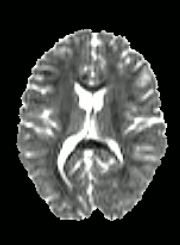

Quality Assessment

DWI

FA

SSE